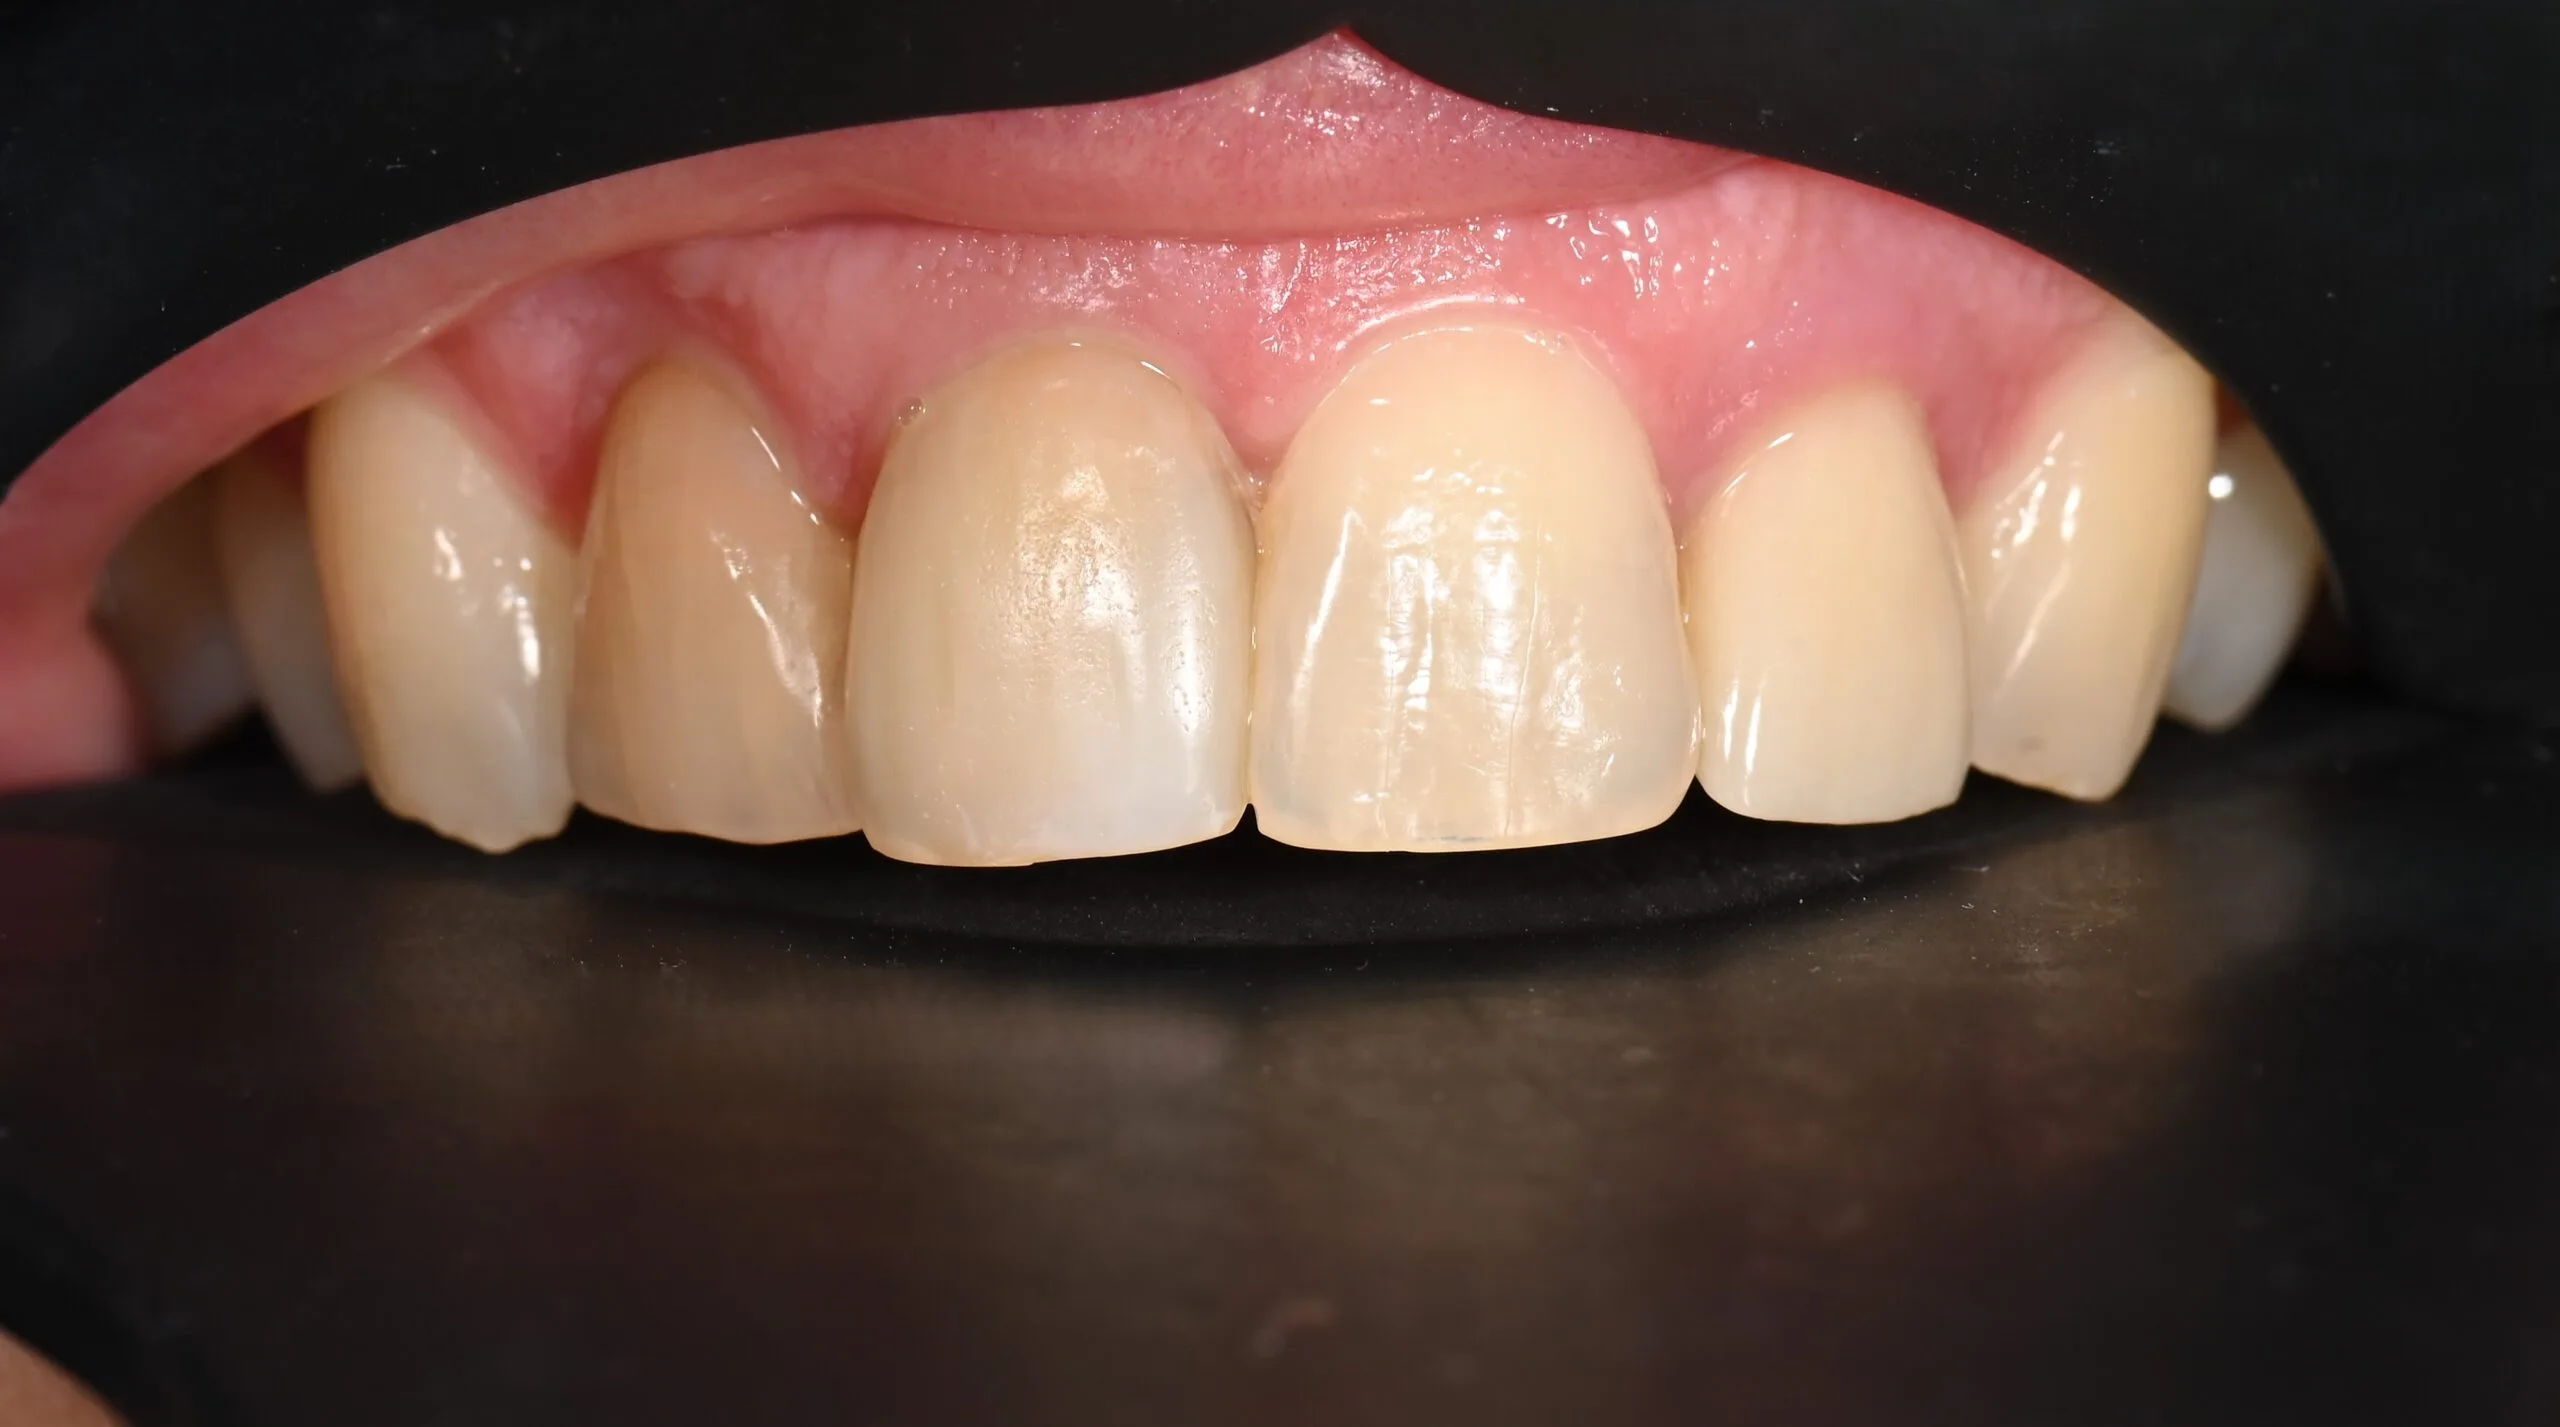

Pacientė kreipėsi dėl skilusių 12 ir 22 dantų šaknų, todėl jautė skausmą ir reikėjo skilusius dantis pašalinti. Pašalinus, buvo įsriegti implantai, jiems prigijus, suformuotos gijimo galvutės ir pritaikyti laikini vainikėliai ant implantų, kad pacientė priprastų prie naujų dantų formos ir pritaikytos spalvos. Net laikinų restauracijų sunku atskirti nuo natūralių dantų ir galime pilnavertiškai džiaugtis savo dantų būkle.